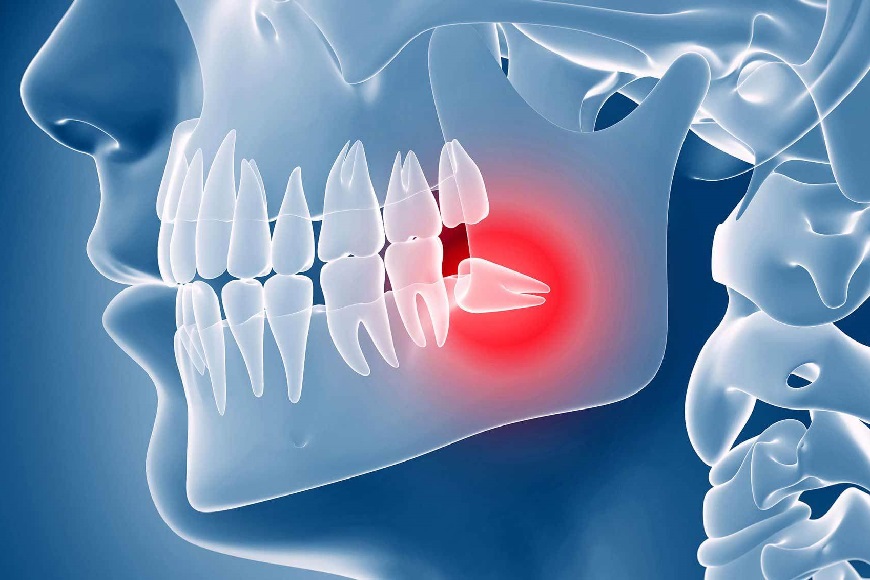

Discorso diverso è quello in cui i denti del giudizio si sviluppano in modo scorretto, creando problemi alla bocca e agli altri elementi della semi arcata di appartenenza. I casi in cui si consiglia un’estrazione sono i seguenti:

• Denti del giudizio storti. Esercitano pressione meccanica sui denti vicini che a differenza degli ottavi sono estremamente importanti. La tensione che si crea può arrivare a muovere e spostare gli altri denti tanto da provocare affollamento dentale, e quindi richiedere un intervento ortodontico correttivo.

• Denti del giudizio inclusi. Può capitare che restino incastrati nell’osso mandibolare o mascellare, ciò può determinare una predisposizione allo sviluppo di cisti.

• Denti del giudizio parzialmente erotti. Questa eventualità fa si restino sommersi a metà nella gengiva, creando un varco in cui possono infiltrarsi residui di cibo e batteri. Il rischio è di sviluppare infiammazioni e carie.

• Malocclusioni causate dai denti del giudizio. Sviluppati possono ostacolare anziché aiutare la masticazione, affaticando l’articolazione temporo-mandibolare. Non sviluppati creano squilibrio tra le arcate, tensioni, dolori e nevralgie dovute allo sforzo compensativo dei muscoli e delle ossa facciali.